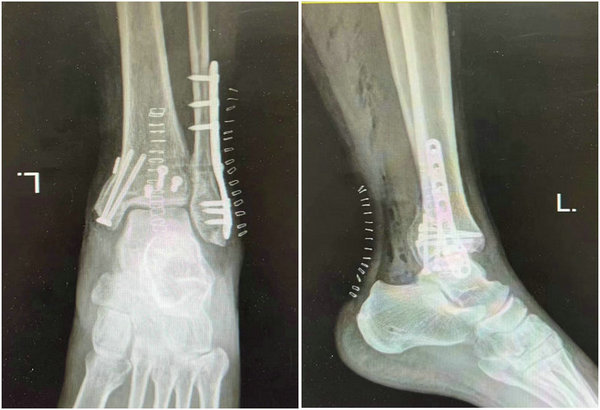

术后X线影像